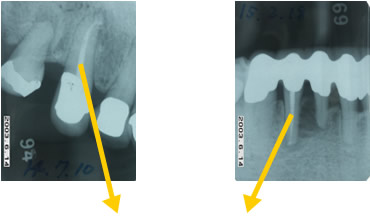

治療例

排膿している歯ぐきの孔に探索用ゴムを挿入し原因部を特定(歯根の先に至る)

歯の中の神経が感染した部分を掃除後、神経が入っていた部分を密閉